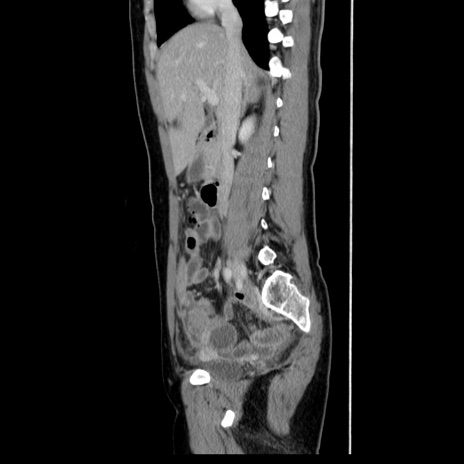

症例39(矢状断像)

【症例】40歳代女性

【主訴】上下腹部痛

【現病歴】2日目から下腹部痛あり。夜間は痛みで眠れなかった。昨日より上腹部痛と下痢が出現。臥位で痛みは軽快したため、休んでいた。本日になって臥位でも立位でも痛みが強くなってきたため救急要請。

【既往歴】子宮内膜症

【身体所見】部:平坦・軟、左上下腹部に圧痛あり、反跳痛あり。

【データ】WBC 21800、CRP 26.78

CT